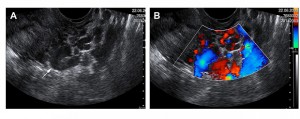

Halk arasında “Renkli Ultrason” diye bilinen Doppler Ultrason bir tür görüntüleme tekniğidir. Doppler ultrasonografide bebeğin uterus damarları ve göbek kordonundan ve bebekteki kan akımlarının incelenmesi ile bebeğin kan akım hızlarındaki azalma yani plasental yetmezlik tespit edilmektedir. Bu görüntüleme tekniğinin asıl amacı bebeği renkli olarak görüntülemek değil kalbin sistol (atım) ve diyastol (dolum) zamanlarında “kan akım hızlarını” incelemektir. Burada görülen renkler bilgisayar ortamında suni olarak oluşturulmuş olan renklerdir ve kan akımının proba yaklaşması ya da probtan uzaklaşmasına göre mavi ya da kırmızının çeşitli tonlarında olmaktadır. Renklendirilmiş kan akımlarını tespit etmek çok daha kolaydır ve saptanmış olan kan akımları dalgalar halinde grafiksel olarak dökümante edildikleri zaman kan akım hızındaki değişiklikler görüntülenebilir ve bazı spesifik oranlama yöntemleri ile subjektif hesaplamalar yapılarak akım hızındaki azalmalar belirlenebilir.